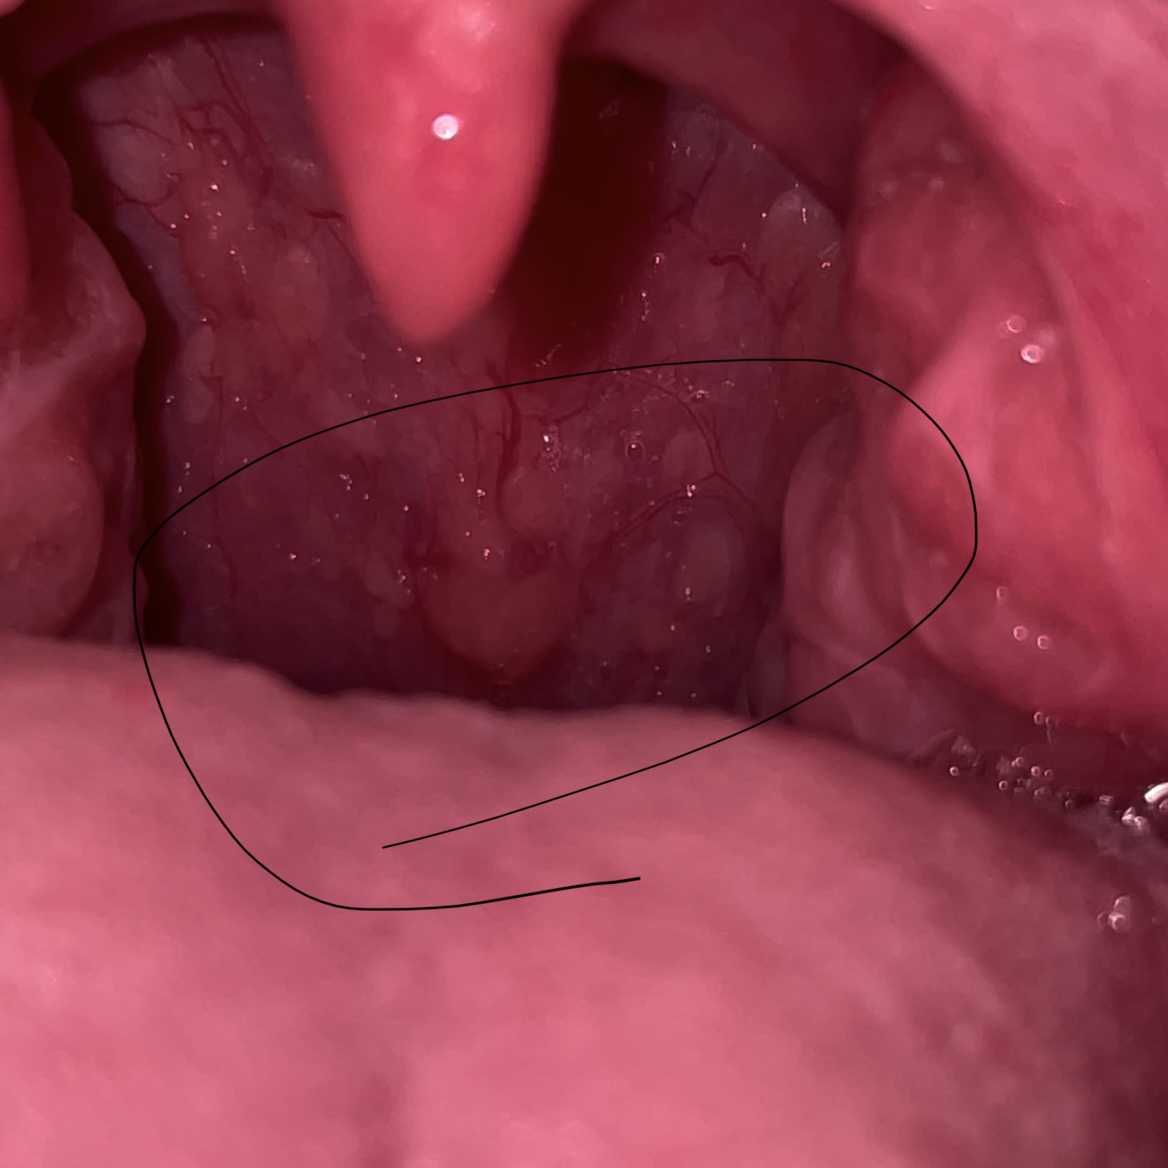

mary_grj مدیر استارتر عضویت: 1401/02/21 تعداد پست: 179 عنوان زائده توی گلو 12107 بازدید | 27 پست سلام کسی که تاحالا همچین چیزی توی گلوش داشته؟ دکتر رفته ببینه چیه؟توی گوگل زده سرطان گلومن از دیشب خواب و خوراک ندارم از استرس نشستم تو گوشی دارم این در و اون در میزنم. حتی توان اینکه پاشم برم دکتر رو هم ندارم 1401/02/21 | 13:12 0 نفر لایک کرده اند ... گزارش تاپیک نامناسب

mary_grj مدیر استارتر عضویت: 1401/02/21 تعداد پست: 179 اون طبیعیه خانم واقعا طبیعیه؟🥺 به اندازه نصف بد انگشته و برجستسگوگل لعنتی هرچیو سرچ میکنی میگه سرطانه

irandokht888 عضویت: 1400/08/09 تعداد پست: 894 لوزه سوم نیست؟ اخطار🚫درخواست دوستی کابر آقا ◀️گزارش و تعلیق کاربری!

mary_grj مدیر استارتر عضویت: 1401/02/21 تعداد پست: 179 گلوت که چیزیش نیس چرا یچیزی اون ته به اندازه نصف بند انگشت هست که برجستس یکم پایین تر از زبون کوچیکه

گیسو_کمندم_۲۲ عضویت: 1399/10/10 تعداد پست: 6520 چرا یچیزی اون ته به اندازه نصف بند انگشت هست که برجستس یکم پایین تر از زبون کوچیکه بنظرم طبیعیه درد داری یا سرفه یعنی منم مامان میشم 😔

دلارام8098 عضویت: 1399/11/25 تعداد پست: 2602 نه تو حالت عادی درد نمیکرد. ولی از دیشب که دیدمش انگار یه توپی توی گلومه داره فشار میاره، مثل غ ... لوزه اس عزیزم ❤درمــــن بـــدمــی مــن زنـــده شـــوم..یـــک جــان چـــه بـــود صــد جـــان مـــنــی..❤